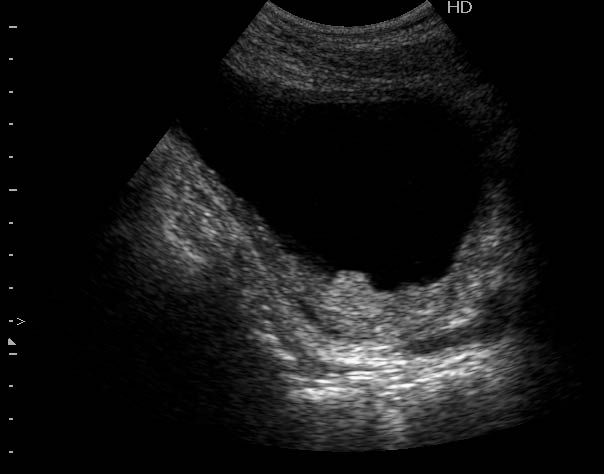

Сравните

Продольное сканирование мочевого пузыря После легкой перкуссии мочевого пузыря

ну... и сравнивать нечего, обычно так выглядят болота в Белоруссии, или первые 2 дня о.цистита